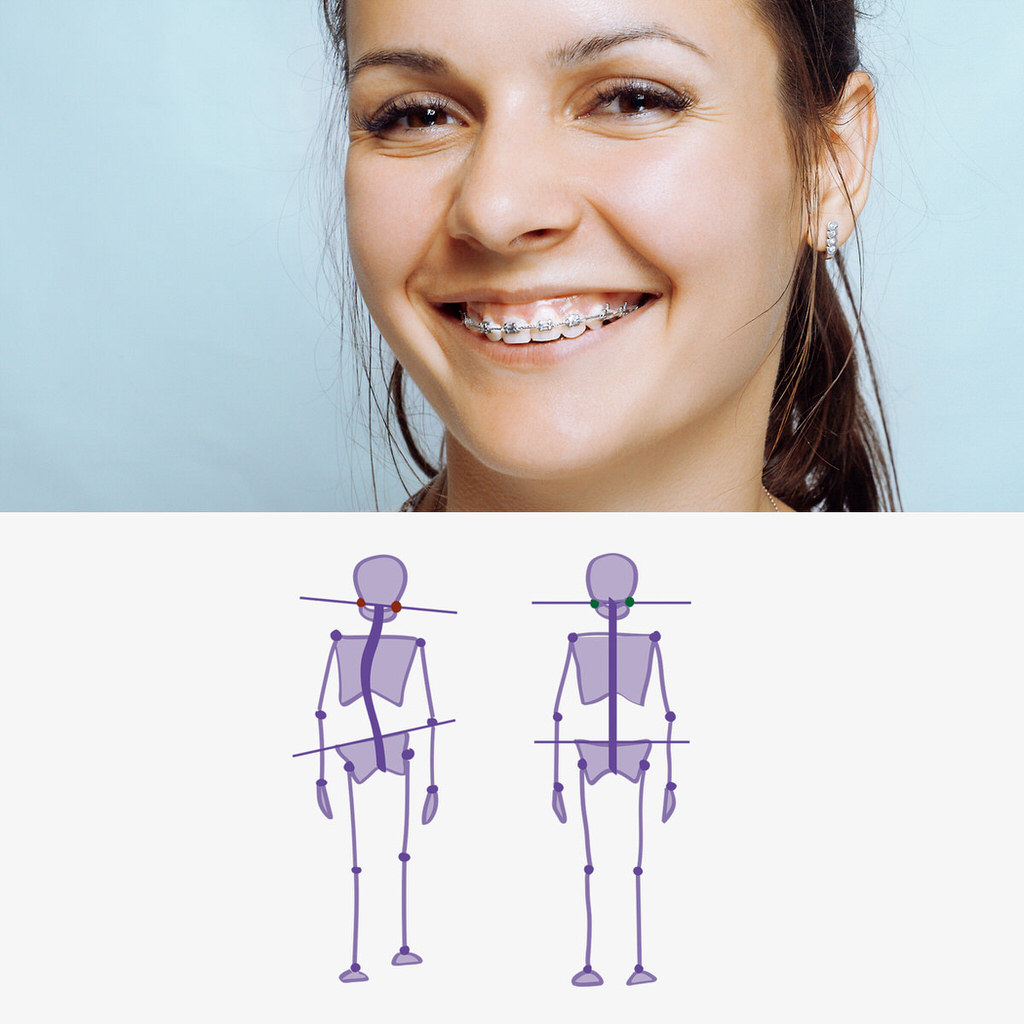

Betroffene nehmen ihr Schnarchen selbst gar nicht oder nur unterschwellig wahr. Tagesmüdigkeit und ein trockener Mund am Morgen sind ein Indiz für das nächtliche Schnarchen. Besonders betroffen ist der Mitschläfer. Eine Schlafapnoe kann gefährliche Auswirkungen wie Bluthochdruck, erhöhtes Herzinfarkt- und Schlaganfallrisiko, Sekundenschlaf am Tage (z.B. beim Autofahren), Depression und gestörte Sexualität haben. Im Schlaf erschlafft die Muskulatur im Rachenraum. Es kommt zum Vibrieren der weichen Gaumenanteile, die Zunge fällt zurück, und es kommt zur Einengung der Atemwege. Mit der Unterkiefer-Protrusionsschiene wird der Unterkiefer vorn gehalten, so dass die Luftwege freibleiben.